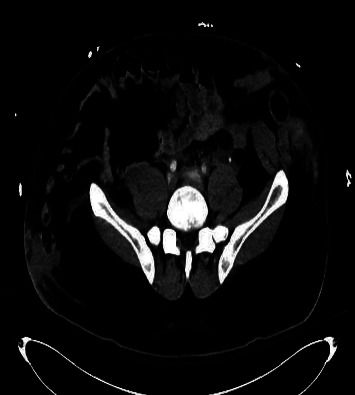

加勒特和布劳恩斯坦提出了机动车碰撞(MVC)受害者 "安全带征兆 "的概念。他们将其定义为腹带造成的腹壁瘀伤。这些创伤征兆并不少见。然而,"安全带综合症",一种因安全装置产生的减速力而导致的肌肉骨骼和内脏器官损伤的模式,却很少见。在此,我们展示了一例因安全带损伤而导致的腹直肌创伤性闭合性断裂。识别这种潜在的损伤非常重要,我们的病例将说明有必要进行仔细的影像检查和临床评估,以识别相关的腹内损伤。

Garrett and Braunstein introduced the concept of the "seat belt sign" in motor vehicle collision (MVC) victims. They defined this as abdominal wall bruising from a lap belt. These signs of trauma are not uncommon. However, "seat belt syndrome," a pattern of musculoskeletal and internal organ injuries resulting from deceleration forces exerted by the safety device is rarely seen. Here, we illustrate a case of traumatic closed rupture of the rectus abdominis muscle secondary to seat belt injury. This potential injury is important to recognize and our case will illustrate the need for careful imaging review and clinical assessment to identify associated intra-abdominal injuries.